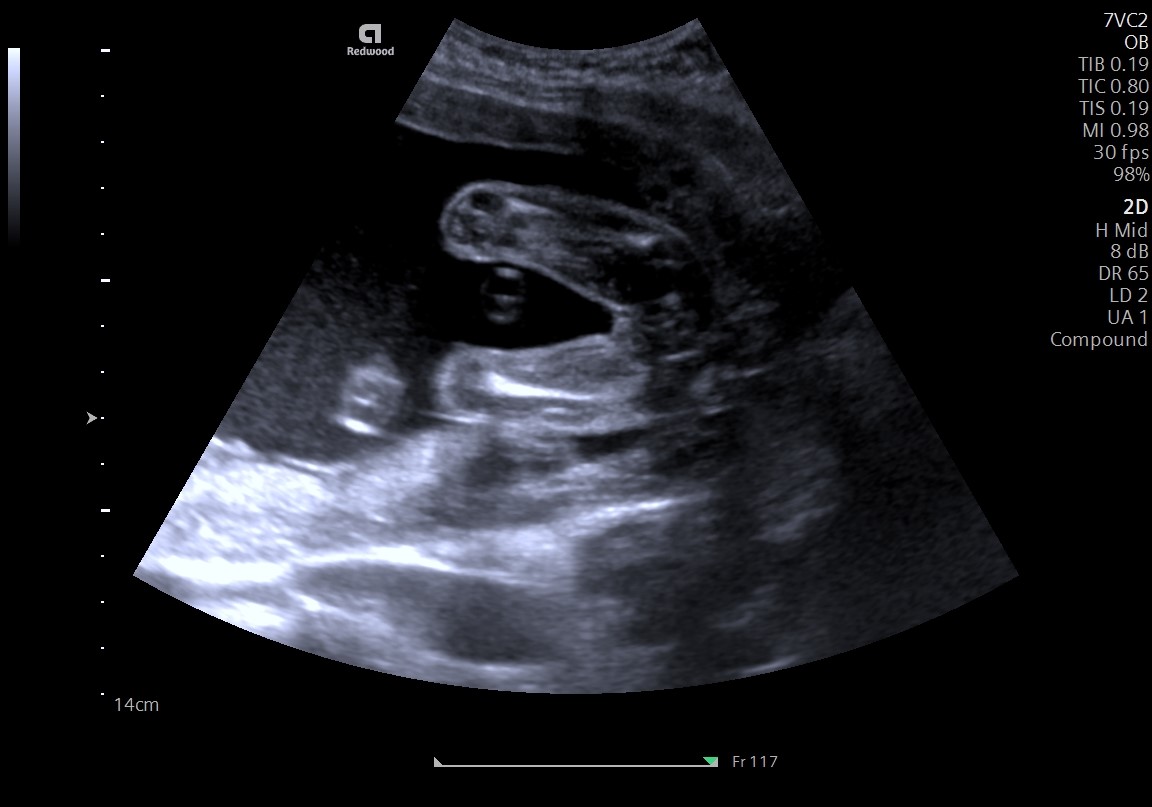

Termijnecho

Tussen de 10 en 12 weken zal de termijnecho plaatsvinden. Voor de 13 weken groeien bijna alle kindjes even hard. Tijdens deze echo wordt je kindje een aantal keer opgemeten waaruit we de definitieve uitgerekende datum kunnen bepalen. Ook zullen we nogmaals kijken of we wellicht meer dan één kindje zien en zullen we kijken naar de hartslag. Om een beter beeld te krijgen is het handig als je met een volle blaas komt. Het is vaak voldoende wanneer je twee uur voor de afspraak niet meer naar het toilet gaat.